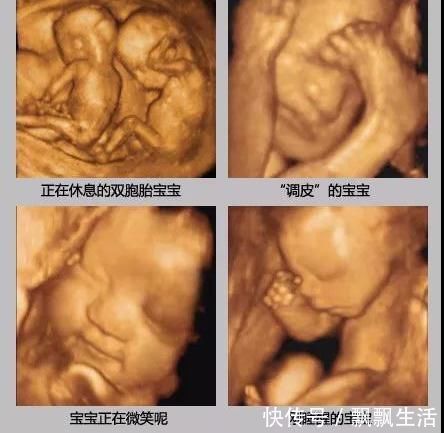

检查时胎儿的“表现”,也可以作为出生后性格的参考,在肚子里就爱搞怪的宝宝,出生后也大多比较淘气。